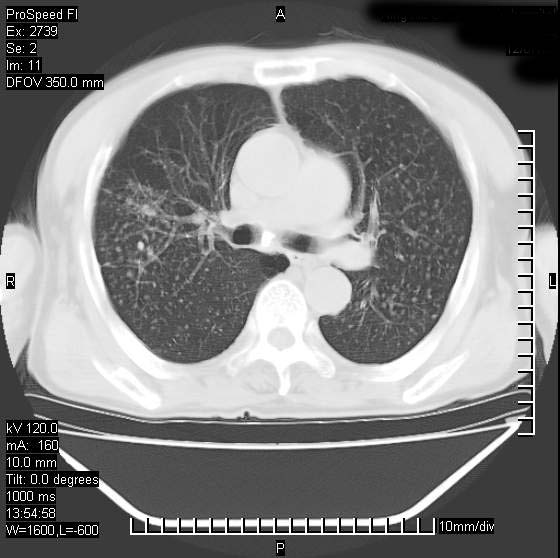

以下是引用andymaomao在2007-12-7 15:54:00的发言:[br]1.双上肺陈旧肺tb灶;[br]2.双中上肺矽肺;[br]3.双肺气肿;[br]4.图中箭头所指乃下腔静脉。

以下是引用山之魂海之韵在2007-12-7 18:59:00的发言:[br]支持矽肺,左肺上叶陈旧性结核,肺气肿。箭头所指乃下腔静脉。下腔静脉显影比主动脉显影迟,增强动脉后迟可以是不均匀的。

以下是引用chengjiaqiu1在2007-12-7 17:49:00的发言:[br]矽肺,左肺上叶陈旧性结核,肺气肿。中箭头所指乃下腔静脉。